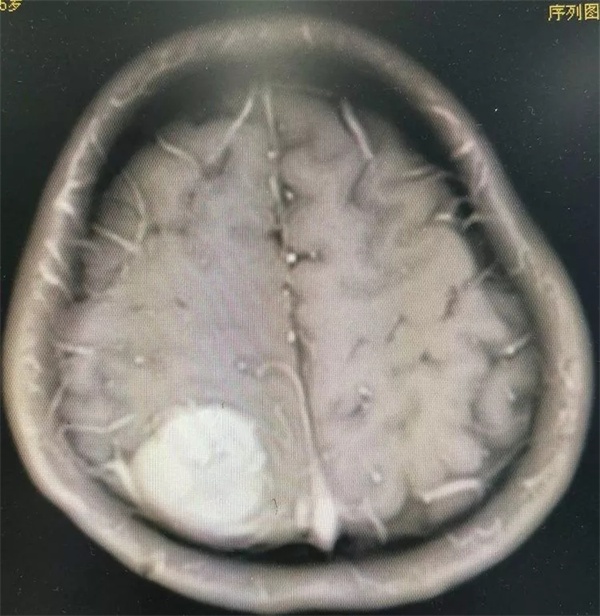

11月28日凌晨一点左右,朱某睡眠正酣,突发四肢抽搐,口吐白沫,双眼上翻,呼之不应,持续数分钟方才停止,睡在一旁的妻子目睹这一切,仿佛经历晴天霹雳,还以为丈夫“被鬼打了” 或“是中邪了”,一时间不知所措。待缓过神后还是拨打120,120把朱某送至捕鱼游戏 神经外科,头颅CT 检查提示右侧顶枕叶类圆形高密度占位,接诊医师姚勇、李世清考虑颅内占位所致继发性癫痫。